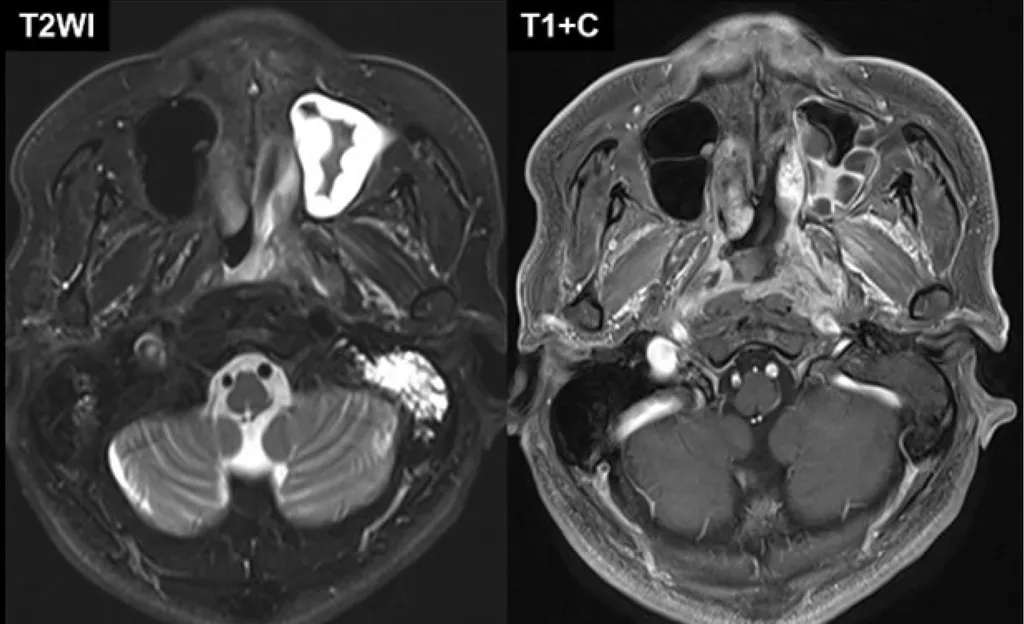

【115-1 醫學(六) 第77題】65 歲糖尿病人,主訴右耳疼痛流膿已 2 週,一天前發燒,右臉腫脹,今天早上右眼瞼下垂。下列敘述何者錯誤?